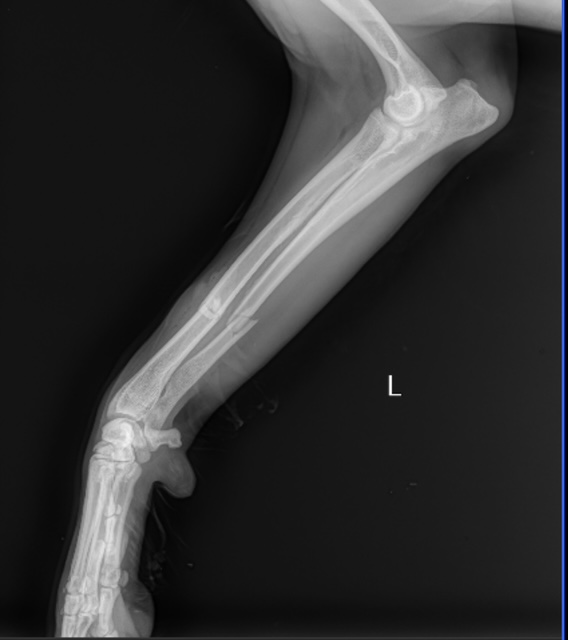

Extracapsular Repair (ExCap)

This procedure stabilizes the knee by placing a strong supportive material outside the joint to limit abnormal movement caused by a torn cranial cruciate ligament. The goal is to restore joint stability, reduce pain, and allow the surrounding tissues to heal and strengthen over time.